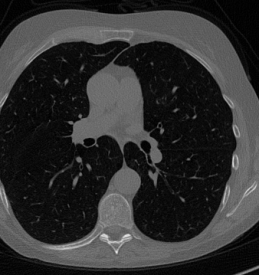

5.1 Results on the real medical images

Here we present the results of RISING applied to the Mayo data set introduced in paragraph 4.1. As previously mentioned, we consider two sparse-view CT geometries, namely P360,360subscript𝑃360360P_{360,360} and P360,180subscript𝑃360180P_{360,180}. In Figure 4 we report the results for the P360,360subscript𝑃360360P_{360,360} protocol, achieved on one image of our test set. The top-left image represents the xRIS=x(15)subscript𝑥𝑅𝐼𝑆superscript𝑥15x_{RIS}=x^{(15)} reconstruction. Even if only a small number of iterations are performed, the main structures of the abdomen are visible; however, the image is still blurry. In the xISsubscript𝑥𝐼𝑆x_{IS} image, shown in the upper-right corner, we notice that the TV regularizer has acted to totally eliminate the artifacts and noise, improving the uniformity of the image in the inner structures. When compared to the ground-truth solution in Figure 2, the contours of the details in xISsubscript𝑥𝐼𝑆x_{IS} appear slightly jagged, differently from xGTsubscript𝑥𝐺𝑇x_{GT} where they are neat but, usually, corrupted by artifacts. The bottom row of Figure 4 shows the two xLPPsubscript𝑥𝐿𝑃𝑃x_{LPP} and xINGsubscript𝑥𝐼𝑁𝐺x_{ING} images, respectively from left to right. It is evident that xLPPsubscript𝑥𝐿𝑃𝑃x_{LPP} has retrieved many details but it presents noisy components, reflecting the features of its target image xGTsubscript𝑥𝐺𝑇x_{GT}. Our solution xINGsubscript𝑥𝐼𝑁𝐺x_{ING} is less corrupted, since the low-contrast regions are correctly preserved and the noise is not visible. These observations are confirmed by Figure 5, which plots the intensity profiles taken over the red line in the second crop (Figure 2). In our approach (on the right) the CNN has accurately learnt the f𝑓f map of (8) and the xINGsubscript𝑥𝐼𝑁𝐺x_{ING} red profile mostly overlaps the black one. On the contrary, the xLPPsubscript𝑥𝐿𝑃𝑃x_{LPP} profile (on the left) is more distant from its target reference.

Figure 4: Results on a test image from the Mayo data set, under the P360,360subscript𝑃360360P_{360,360} CT protocol. Top-left: xRISsubscript𝑥𝑅𝐼𝑆x_{RIS}; top-right: xISsubscript𝑥𝐼𝑆x_{IS}; bottom-left: xLPPsubscript𝑥𝐿𝑃𝑃x_{LPP}; bottom-right: xINGsubscript𝑥𝐼𝑁𝐺x_{ING}.